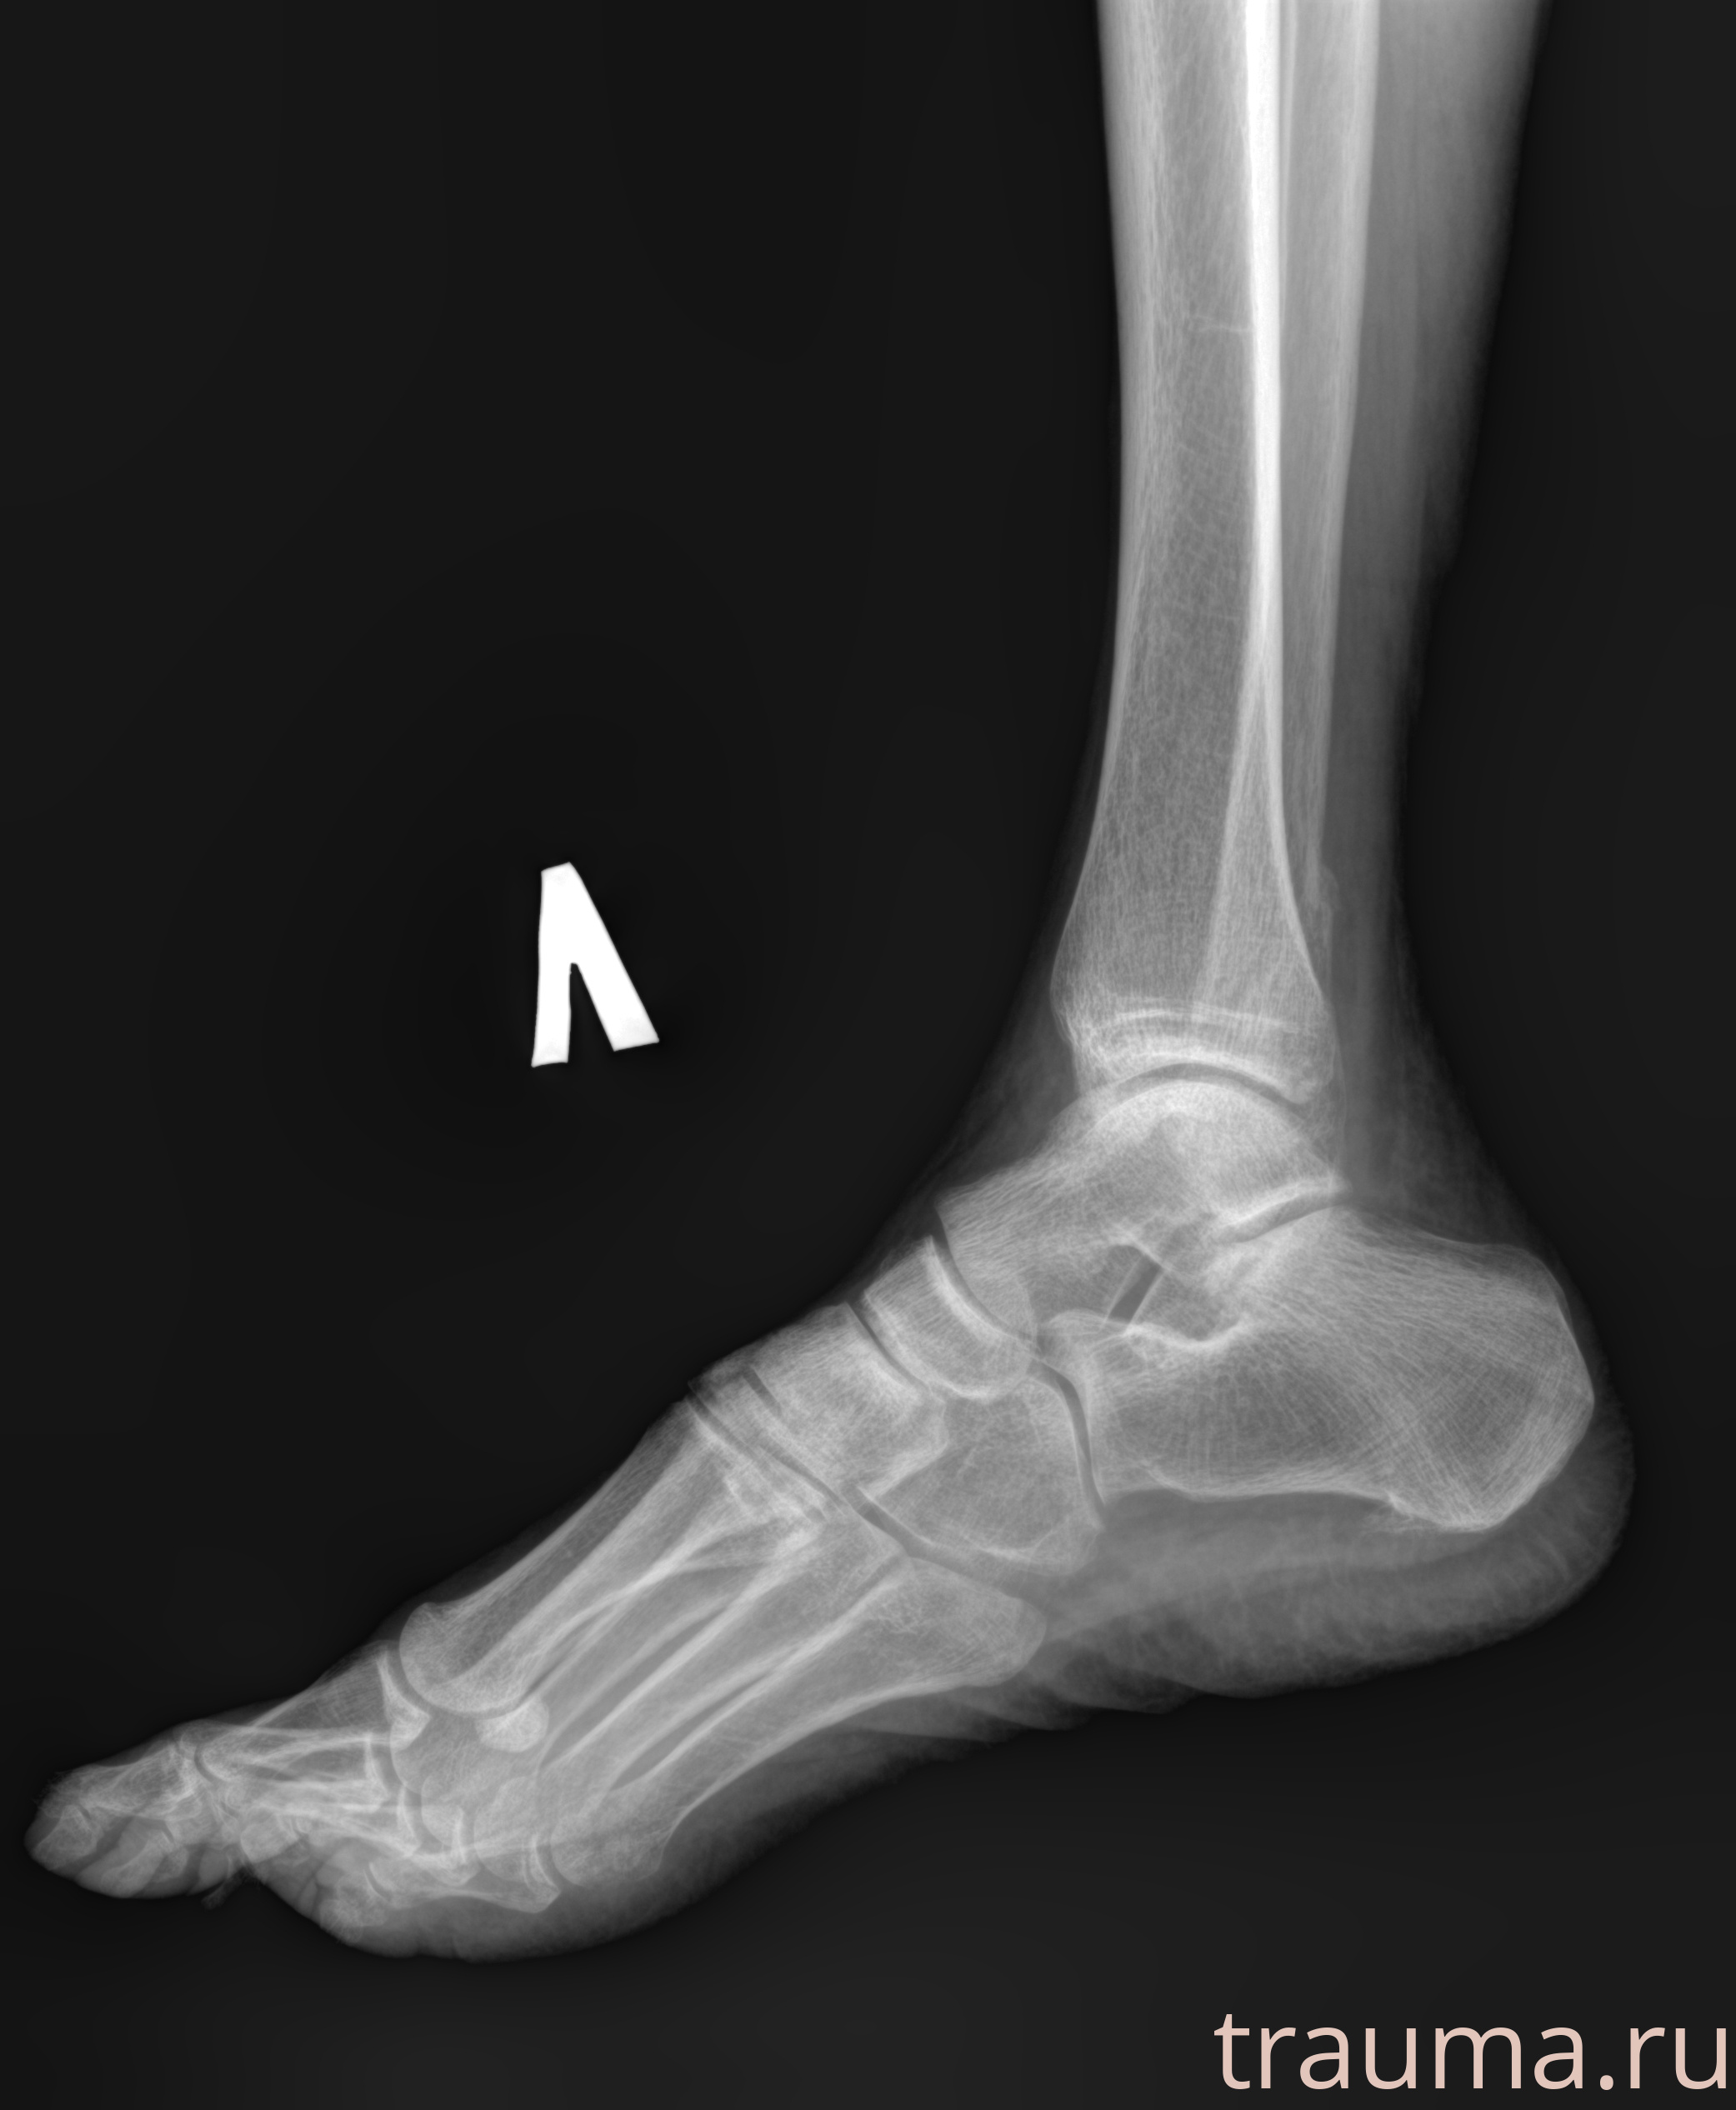

Рентгенограммы

Рентген на дому: по вашему адресу приезжает врач-рентгенолог, травматолог-ортопед с мобильным рентгеновским аппаратом, проводит диагностику травмы или заболевания, делает необходимые рентгенограммы, дает рекомендации по дальнейшему лечению. Получить качественные снимки в домашних условиях возможно благодаря уникальной методике, разработанной МосРентген Центром для института  Склифосовского